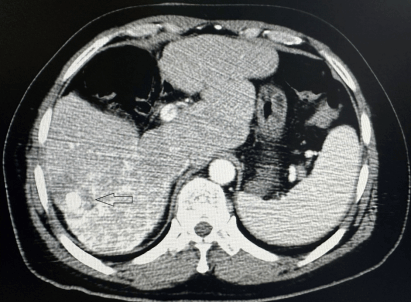

【佑安援藏】大病不出藏,北京佑安医院援藏专家李建军助力拉萨市人民医院开展首例肝癌微波消融术

患者是一名56岁藏族男性,因“丙肝史6年,发现肝占位10天”入院。患者既往有丙肝史,予抗病毒治疗后好转。10天前在外地医院查核磁发现肝内占位,考虑肝癌可能,建议行手术切除治疗,但患者拒绝。遂转诊至拉萨市人民医院援藏专家李建军主任医师门诊,李主任结合患者病史及影像资料,认为肝癌诊断明确,建议患者行肝动脉化疗栓塞术序贯肝肿瘤微波消融术。但患者不放心拉萨市人民医院的设备和医疗水平,执意想去北京治疗。李建军主任耐心地和患者解释,说明医院使用的是目前国内最先进的医疗设备,同意亲自为患者手术,并说明消融术是一种根治性治疗方法,和外科手术切除、肝移植一样都是肝癌的三大根治性治疗方法之一,且具有微创、费用低、术后恢复快等优势。患者及家属欣喜同意住院治疗。

图1 红色圆圈内为肝癌病灶